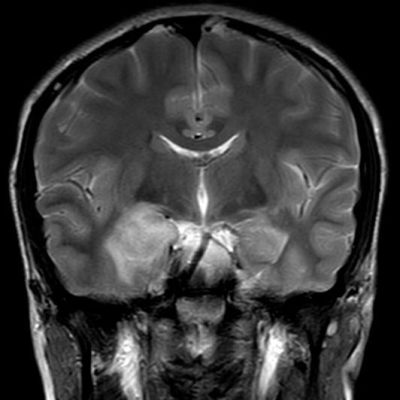

- A) Sağ temporal lob anteromedialinde silik sınırlı BT’de hipodens (ok), MRG’de T2AG ve FLAIR hiperintens (oklar), T1AG izo-hipointens (ok) sinyal özelliğinde ekspansil kitlesel lezyon izlenmektedir.

- B) Lezyon difüzyon görüntüde izo-hiperintens, ADC haritalamada hafif hiperintens izlenmiş olup (oklar) diffüzyon kısıtlılığı göstermemektedir. Lezyonun anterior kesiminde kontrastlı serilerde yamalı kontrast tutulumları (oklar) mevcuttur. MR spektroskopide lezyon düzeyinden elde olunan multivoksel görüntülerde kolin pikinde artış ve NAA da azalma (oklar) dikkati çekmektedir. Kolin/kreatinin oranı 1.76 olarak ölçülmüştür.

- BT: Spesifik olmayan kitle bulgularıdır. İzo-hipodens olarak izlenir. Kitle %35 oranında kalsifikasyon gösterebilir. Olgumuzda kalsifikasyon izlenmemiştir. Kemik remodelasyonu da eşlik edebilir.

- MRG: T1A serilerde solid komponent izo-hipointens, T2A serilerde genellikle hiperintens sinyalde görülür. Peritümöral T2/FLAIR hiperintens kitle ödemi oldukça nadirdir. T1 C+ görüntülerde solid komponentte değişken oranda kontrastlanma ,T2*(SWI) serilerde eğer kalsifikasyon eşlik etmekteyse buna bağlı blooming artefaktları görülebilir.